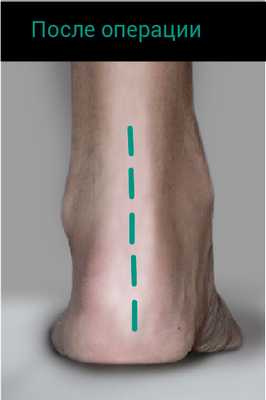

- Признак «слишком много пальцев». Если смотреть на стопу со стороны спины пациента, обычно мы видим только пятый и половину четвертого пальца стопы. При плоскостопии мы увидим большее число пальцев.

![симптом слишком много пальцев]()

У данного пациента имеет место дисфункция сухожилия задней большеберцовой мышцы с развитием плоскостопия. Передний отдел стопы направлен наружу. Симптом «слишком много пальцев». При осмотре стопы сзади мы 3,4,5 палец стопы.